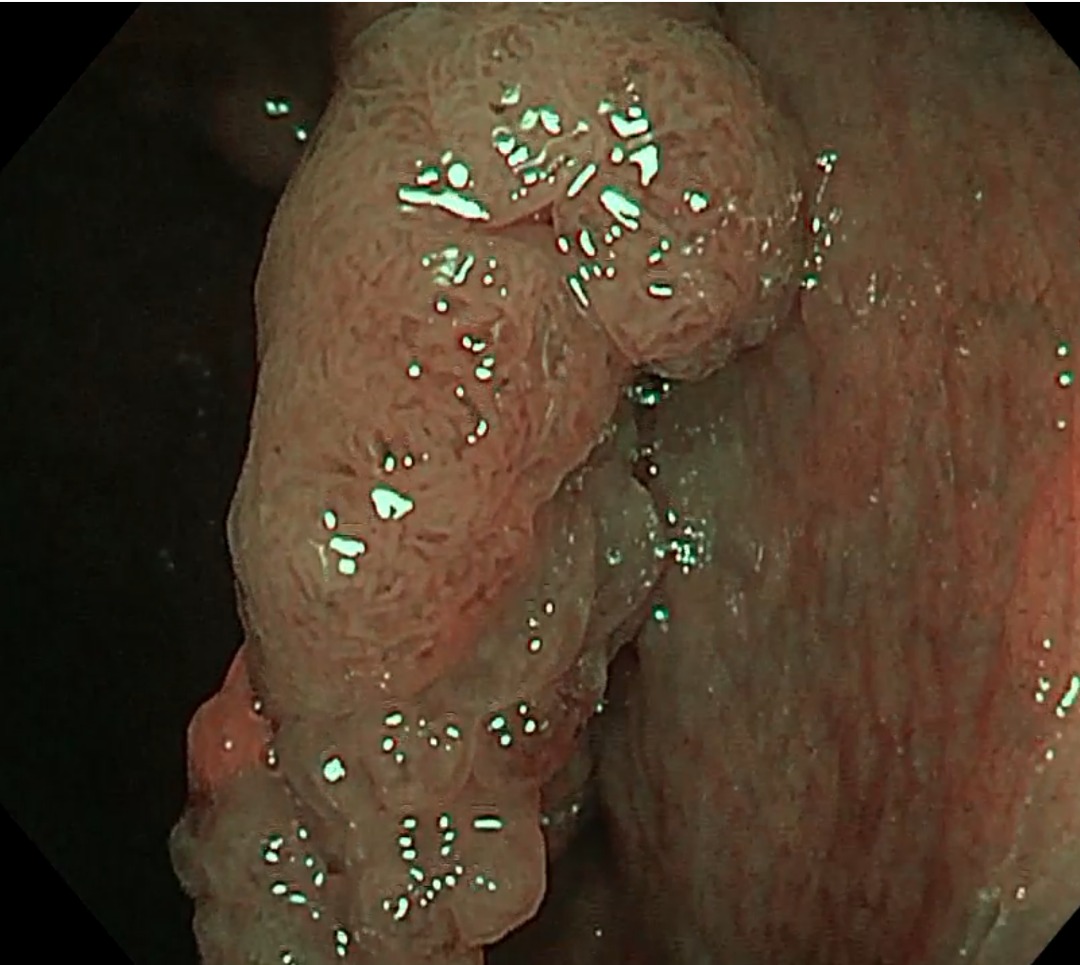

并非所有类型的大肠瘤都会变成癌症,因此,准确辨识至关重要。以现今的内视镜技术,在放大20至30倍后,已能清楚观察黏膜表面的微结构、微血管的形状,以及表面的排列样貌。若黏膜或血管出现不规则增生(图4),也能初步判断肿瘤的类型。

不会癌变的类型,如增生性息肉,一般不需要特别处理;若是腺瘤性息肉(adenomatous polyps,图5),尤其体积超过1公分、呈绒毛状,或伴有不典型增生,就有癌变的风险。